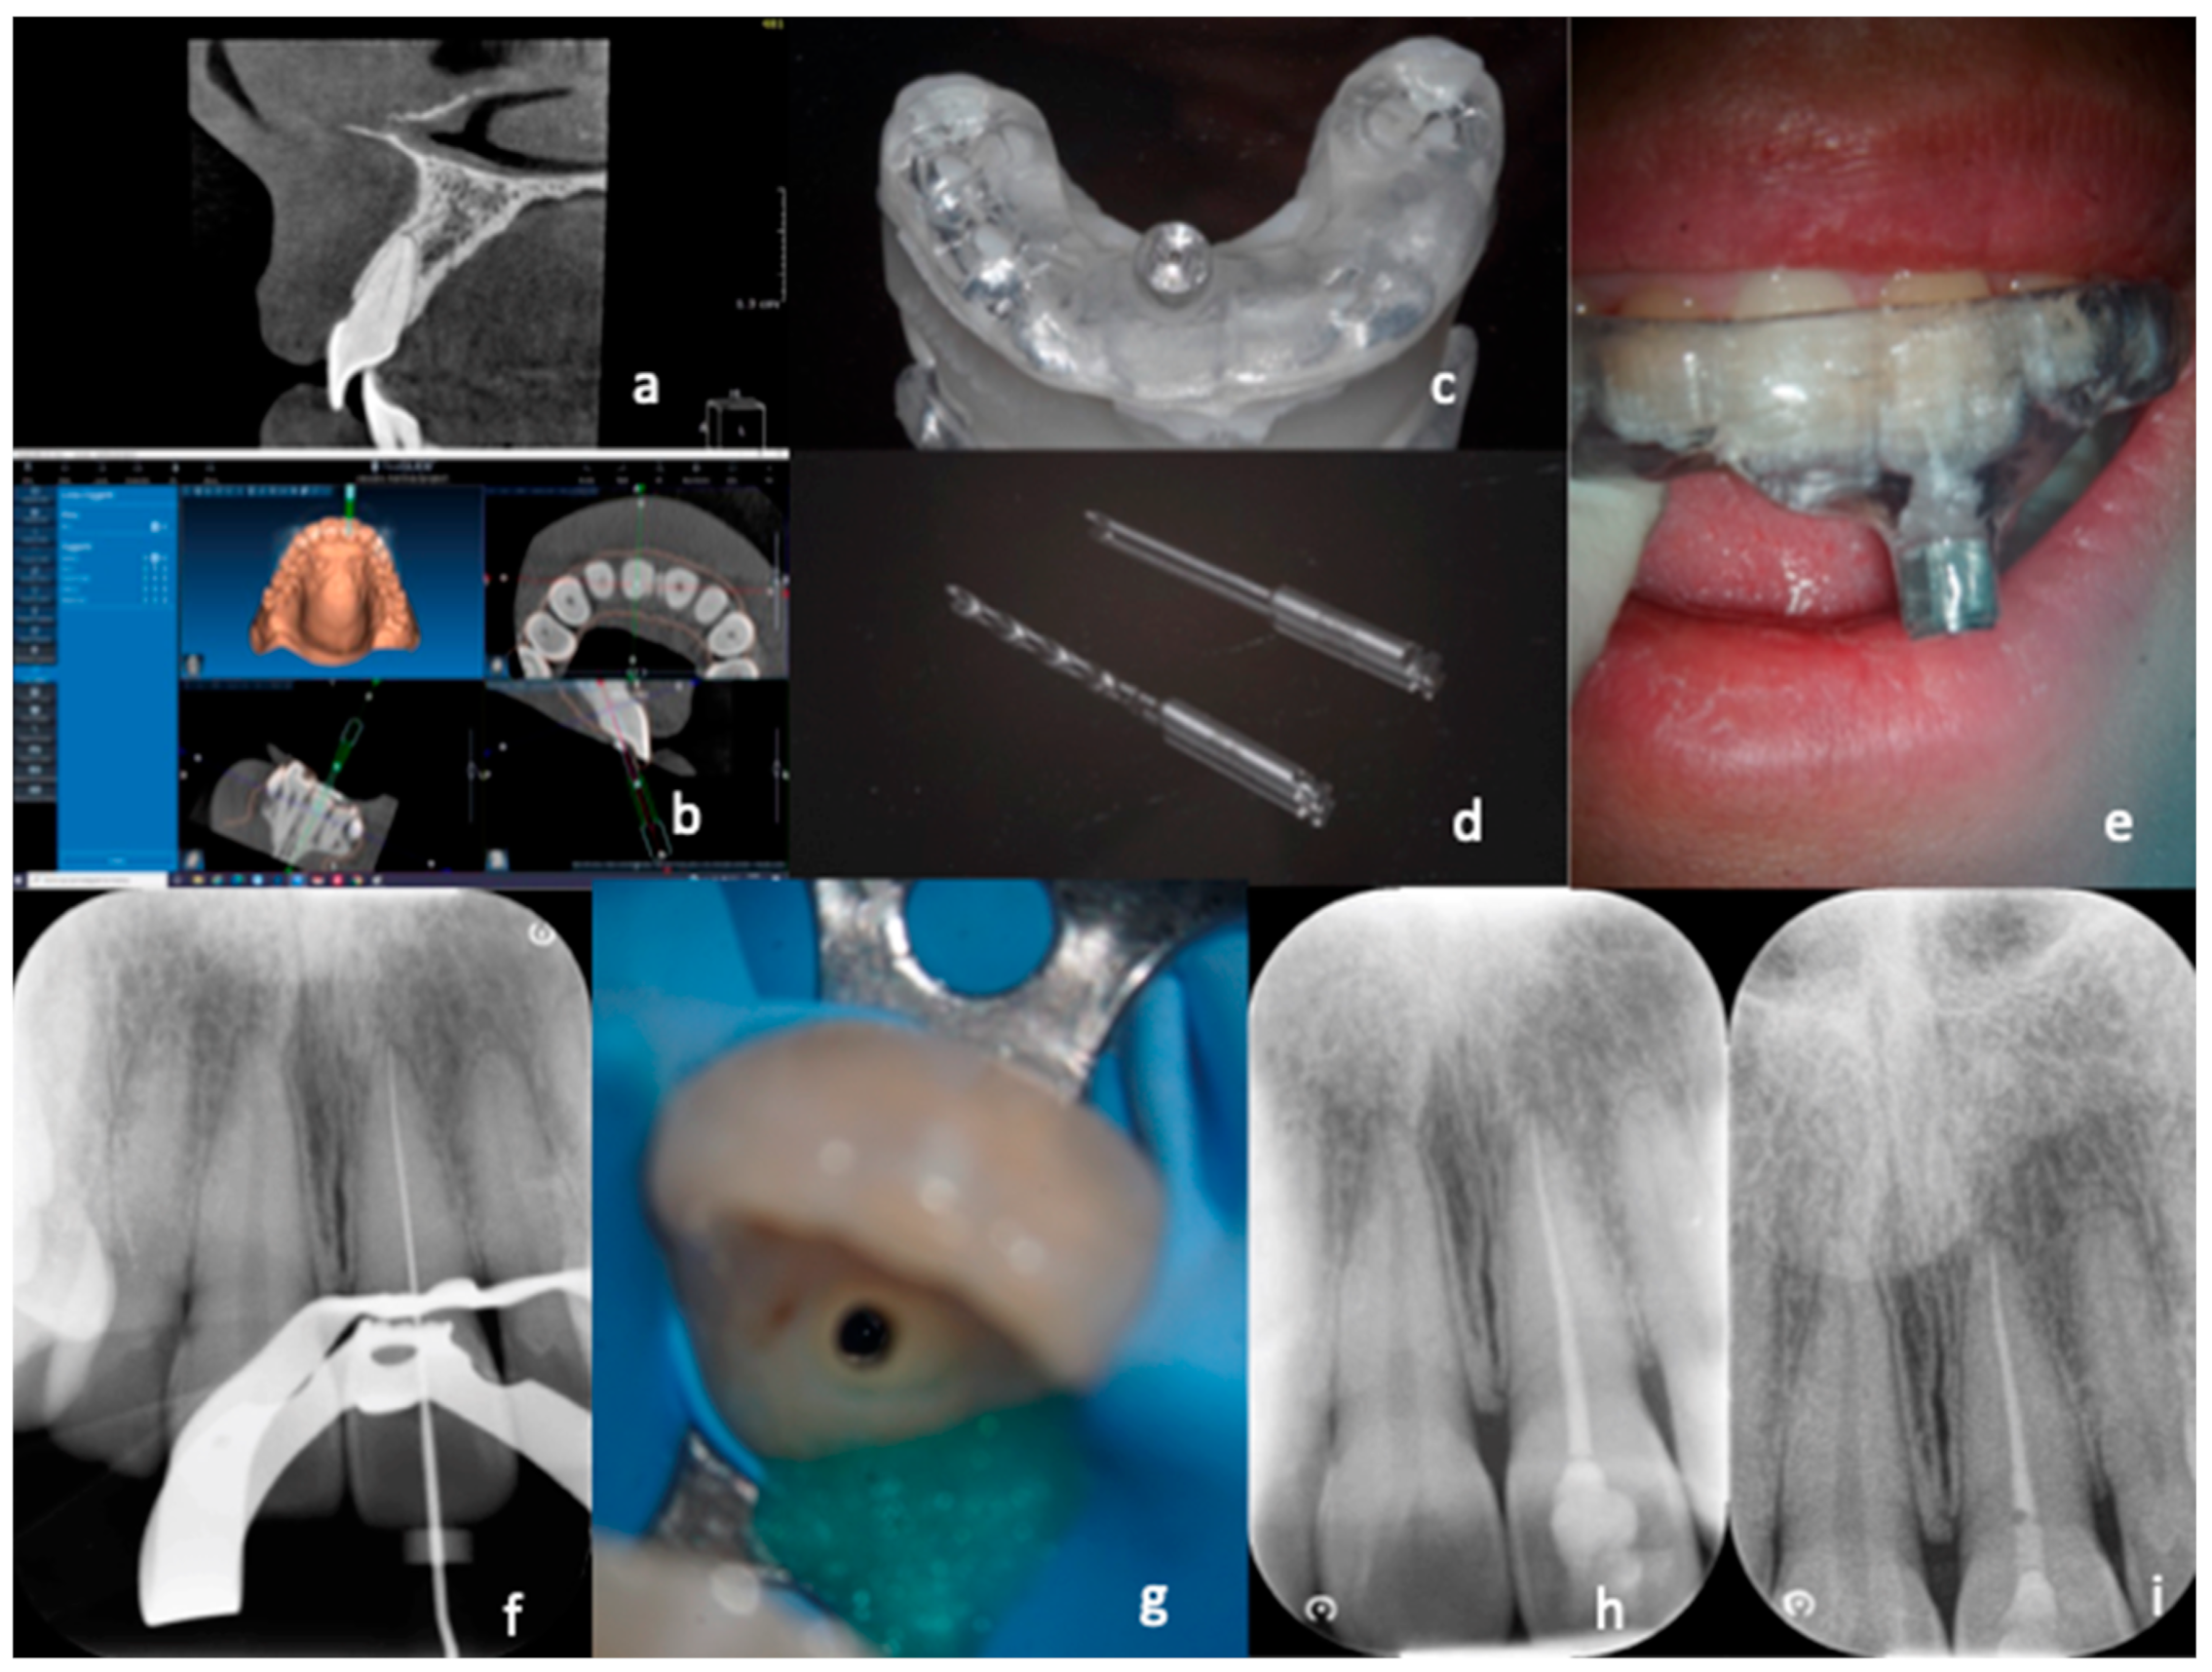

Figure 2. Treatment with “acceptable precision” of a calcified canal. The CBCT scan (a) and the optical impression were performed in this case. First, the data were processed to provide a virtual design of the guide (b), and then the artifact was created that was placed in position in the patient’s arch (c). Next, the drill was inserted up to the end of the “limit stop” and then, after several attempts, not finding the canal, a CBCT (d,e) was performed, which allowed highlighting of the position of the maximum penetration of the drill with respect to the patent canal. Finally, with the help of the microscope and ultrasound, the canal was found (f), shaped, and obturated (g).

For what regards those elements in which the canal was not immediately reached after the complete penetration of the bur (Figure 2), after several attempts made with the C+ steel instruments, two intraoral X-rays were carried out in different projections to locate the most apical point reached by the bur in relation to the beginning of the patent canal. In cases where it was impossible to reach the canal, a second CBCT examination according to a previous study [17] was carried out, with the same characteristics as the diagnostic one, requiring the patient to give written consent to this examination, as already stipulated in the first informed consent form.

The purpose was to understand where the tip of the bur ended up and the relationship of the patent channel with the point reached. For this purpose, the axial sections of the volumetric examination were primarily used. After the distance between the patent canal and the endpoint of the bur was recorded, the canal was widened using thin ultrasonic tips (ET 20-Satelec, Acteon, Merignac, France) in the direction of the point of canal patency under the control of the operating microscope (Pico-Zeiss, Oberkochen, Germany). Once access to the patent canal was detected, the endodontic treatment was carried out in the same way as indicated for the treatment of the canal with an optimal course.